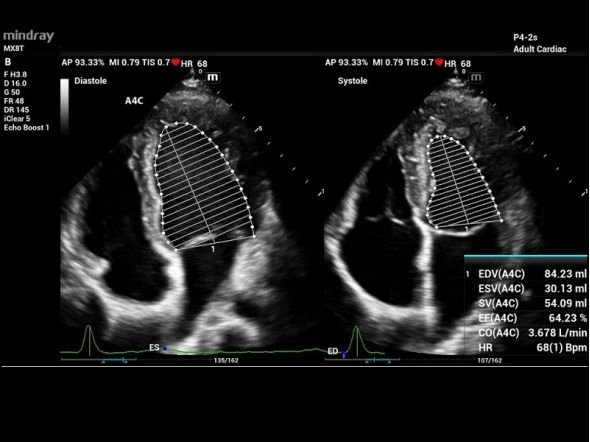

Auto EF

- Автоматическое распознавание A2C или A4C

- Автоматическое распознавание границы эндокарда

- Автоматическое распознавание диастолических и систолических значений

Сердечный цикл